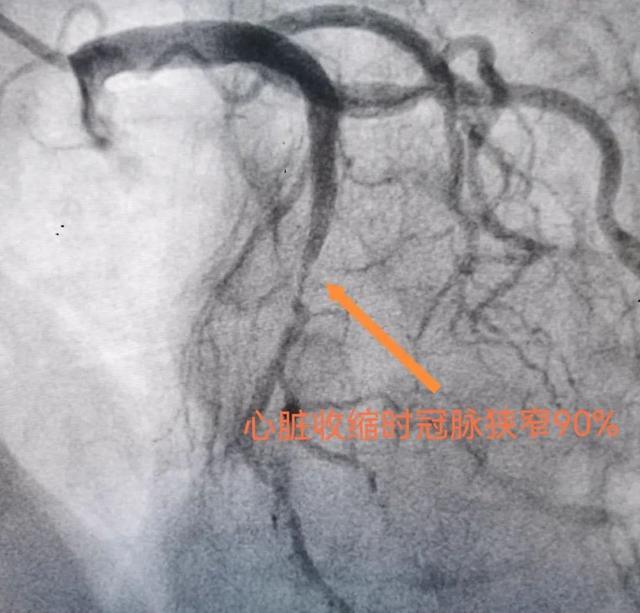

最近,李阿姨因为反复胸痛,入住湖南省中西医结合医院(湖南省中医药研究院附属医院)心血管内三科。经过冠脉造影检查后,结果提示:左前降支心肌桥,收缩期狭窄90%。

壁冠状动脉在心脏收缩期往往受到心肌组织压迫而管腔缩窄,舒张期时压迫解除而恢复充盈,被称为“挤奶现象”。大部分人都没有症状,当出现了一些胸闷、胸痛的症状到医院检查,尤其是做冠脉CT成像、冠脉造影、冠脉内超声等检查时才会被诊断。